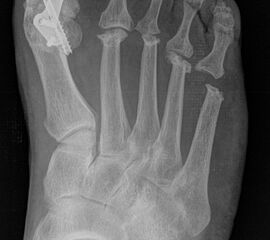

Deutlich bessere Ergebnisse wurden erreicht durch eine Kombination der OP nach Tillmann mit einer Arthrodese des Großzehengrundgelenks oder auch einer Lapidus-Arthrodese 611. Dies wurde bereits 1956 durch Vainio empfohlen, hat sich aber erst in diesem Jahrtausend flächendeckend durchgesetzt 121314.